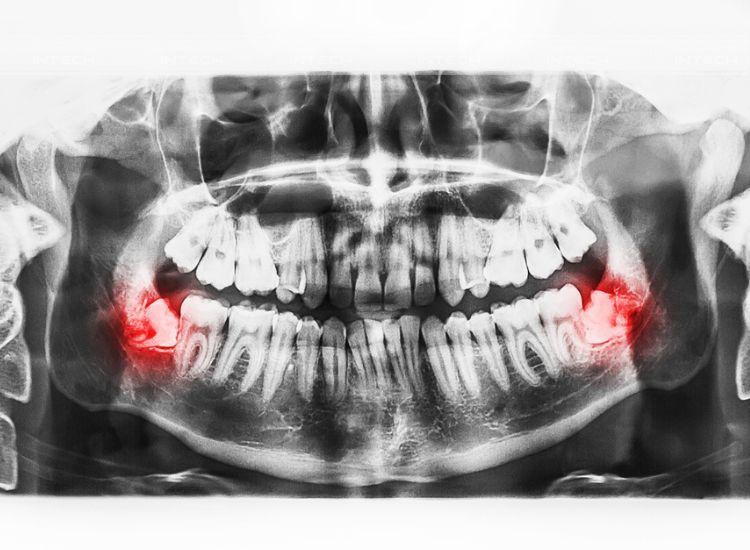

Tại đây, bác sĩ sẽ kiểm tra tổng quát tình trạng răng miệng để loại trừ các bệnh lý răng miệng. Sau đó, bác sĩ sẽ chụp phim X-quang để xác định hướng mọc, số lượng mọc của răng khôn để lên kế hoạch điều trị phù hợp.

• Răng 8 mọc lệch, có xu hướng xô vào răng hàm số 7 gây đau, nhiễm trùng trong thời gian dài

• Răng khôn mọc thẳng nhưng không có răng đối diện sẽ khiến sai lệch khớp cắn, xô lệch cả hàm răng